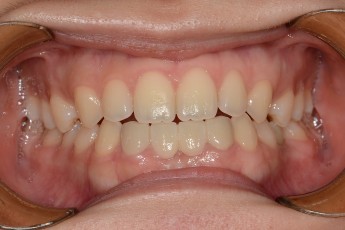

Before

After